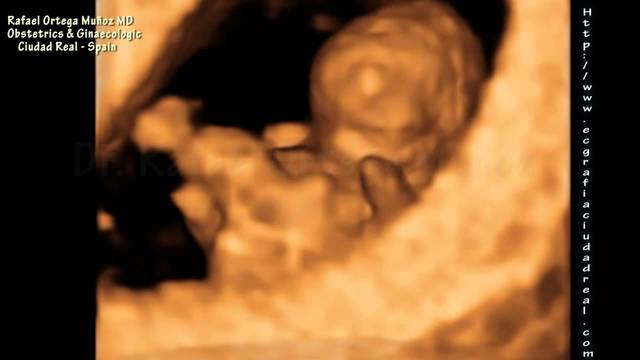

• 20 SEMANA

20 SEMANA

El feto pesa entre 280gramos y 350 gramos. El vello, llamado lanugo, se distribuye por casi toda la piel. Ésta se cubre de la vernix caseosa. Comienzan a salir las uñas y los pelos en la cabeza. El feto se pone el pulgar en la boca desarrollando más el reflejo de succión. Cuando la madre descansa el bebé se mueve, porque no tiene presión externa, y a la inversa, cuando la madre se mueve se acurruca para protegerse y no lastimarse.